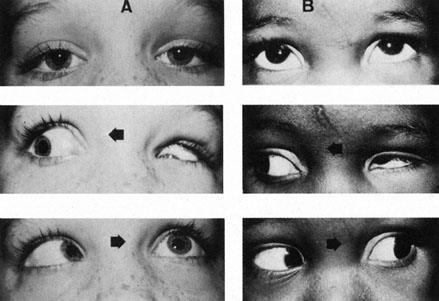

innervation in Duane's syndrome and related congenital ocular

motor disorders. Am J Ophthalmol 60:443, 1965 69. Phillips WH, Dirion JK, Graves GO: Congenital bilateral palsy of abducens. Arch Ophthalmol 8:355, 1932 70. Blodi FC: Electromyographic evidence for supranuclear gaze palsies. Trans Ophthalmol See UK 90:451, 1970 71. Demer JL: The orbital pulley system: a revolution in concepts of orbital anatomy. Ann NY Acad Sci 956:17, 2002 72. Demer JL: Ocular kinematics, vergence, and orbital mechanics. Strabismus 11:49, 2003 73. Kono R, Clark RA, Demer JL: Active pulleys: magnetic resonance imaging of rectus muscle paths in tertiary

particolare riguardo alla patogenesi. Rass Ital Ottal 15:345, 1946 80. Hotchkiss MG, Miller NR, Clark AW, Green WR: Bilateral Duane's retraction syndrome: a clinical-pathologic case

report. Arch Ophthalmol 98:870, 1980 81. Miller NR, Kiel SM, Green WR, Clark AW: Unilateral Duane's retraction syndrome (type 1). 100:1468, 1982 82. Mims JL III: Describing Duane's retraction syndrome. Binoc Vis Strabismus Q 17:86, 2002 82A. Thomas R, Mathai A, Gieser SC, et al: Bilateral synergistic divergence. J Pediatr Ophthalmol Strabismus 30:122, 1993 83. Scott AB, Wong GY: Duane's syndrome: An electromyographic study. Arch Ophthalmol 87:140, 1972 84. Pressman SH, Scott WE: Surgical treatment of Duane's syndrome. Ophthalmology 93:29, 1986 85. Raab EL: Clinical features of Duane's syndrome. J Pediatr Ophthalmol Strabismus 33:64, 1986 86. Hoffman RJ: Monozygotic twins concordant for bilateral Duane's retraction syndrome. Am J Ophthalmol 99:563, 1985 87. Chew CKS, Foster P, Hurst JA, et al: Duane's retraction syndrome associated with chromosome 4g27-31 segment

deletion. Am J Ophthalmol 119:807, 1995 88. Cullen P, Rodgers CS, Callen DF, et al: Association of familial Duane anomaly and urogenital abnormalities with

a bisatellited marker derived from chromosome 22. Am J Med Genet 47:925, 1993 89. Tredici TD, von Noorden GK: Are anisometropia and amblyopia common in Duane's syndrome? J Pediatr Ophthalmol Strabismus 22:23, 1985 90. Osher RH, Schatz NJ, Duane TD: Acquired orbital retraction syndrome. Arch Ophthalmol 98:1798, 1980 91. Miller GR, Glaser JS: The retraction syndrome and trauma. Arch Ophthalmol 76:662, 1966 92. Kivlin JD, Lundergan MK: Acquired retraction syndrome associated with orbital metastasis. J Pediatr Ophthalmol Strabismus 22:109, 1985 93. Rubenstein AE, Lovelace RE, Behrens MM, Weisburg LA: Möbius syndrome in association with peripheral neuropathy and Kallman